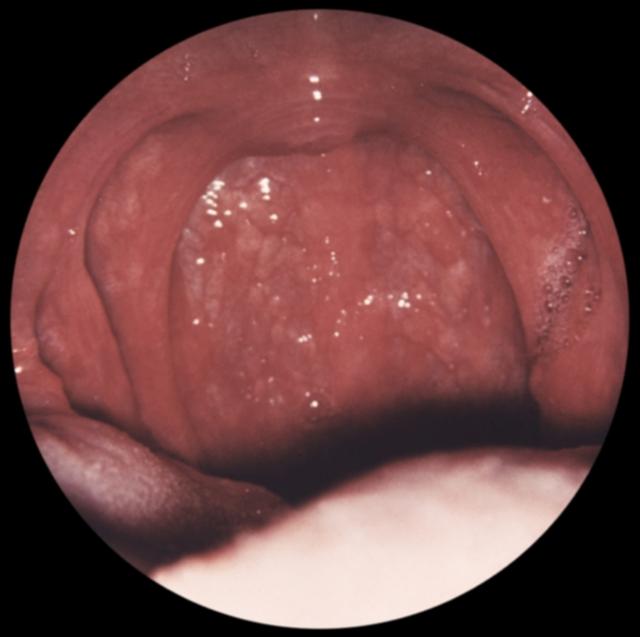

Рис. а). Вид зева при остром фарингите.